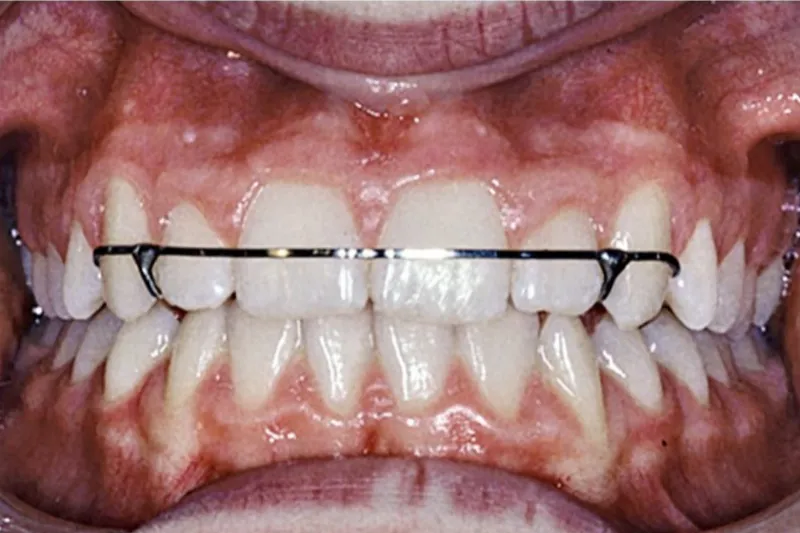

Når den aktive ortodontibehandling afsluttes, begynder retentionsfasen. Denne del afhænger af, hvilken type ortodontibehandling der er udført, og især af, hvilke bidkorrektioner der er foretaget. Afhængigt af disse forhold vælger man enten fastsiddende eller aftageligt retentionsapparatur. Patientens alder under behandlingen og den forventede længde på retentionsperioden er også vigtige faktorer, når man beslutter, hvilken type retentionsapparatur der skal anvendes. De aftagelige apparaturer er lette at anvende for patienterne, men de forudsætter god kooperation og regelmæssige kontroller, da apparaturerne slides og undertiden må udskiftes. Fordelene ved retentionstråd er, at den sidder fast på tænderne, og at kravene til kooperation er mindre, men også dette apparatur skal kontrolleres regelmæssigt. Selv efter mange års retention kan man ikke forvente, at status quo bevares, når retentionsperioden er slut. Kroppens normale aldring påvirker også kæber og tænder, og livslang retention kan derfor være påkrævet, hvis patienten fortsat vil have lige tænder og regelmæssige tandbuer. Det er rimeligt, at den alment praktiserende tandlæge tager ansvar for retentionskontrollerne, sørger for reparation og eventuelt udskiftning af bondede retainere, kontrollerer pasform og eventuelt udskiftning af aftageligt retentionsapparatur samt motiverer patienterne til at anvende og pleje deres apparatur.

When active treatment is completed, the retention phase starts. This period is dependent on what type of orthodontic treatment has been performed, but above all on which malocclusions that have been treated. Depending on the chosen treatment, the choice is either removable or fixed retention. The patients age at treatment and the calculated length of the retention period is also important in choosing the type of retention appliance. Removable appliances are easy to use, but demand good cooperation and regular controls, because they are easily worn out and sometimes need to be redone. The advantages of retention wires are that they are fixed, and less cooperation is needed. None the less these wires and the occlusion have to be monitored. Regardless of how many years of retention follow, one cannot expect that nothing changes in the occlusion after the end of the retention period. The natural aging of the of the body also includes the jaws and teeth and demands therefore lifelong retention if the patient wants permanent straight and aligned front teeth. It is fair to assume that the general practitioner will take responsibility for the retention controls and when needed, repair or renew bonded retainers, control the fit of removable appliances and when needed replace them with new ones and also motivate the patients in wearing and taking care of their appliances.